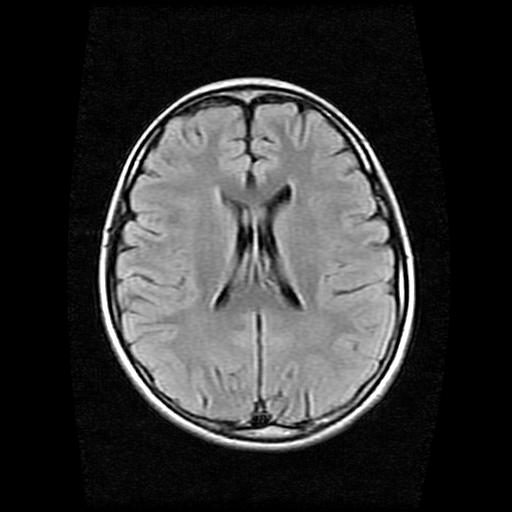

9岁女孩,三岁时诊断为癫痫,一直服丙戊酸钠,现患者一般情况良好,家长复查核磁片,看能否停药..

巨脑回

未见异常信号灶.

未发现异常信号。